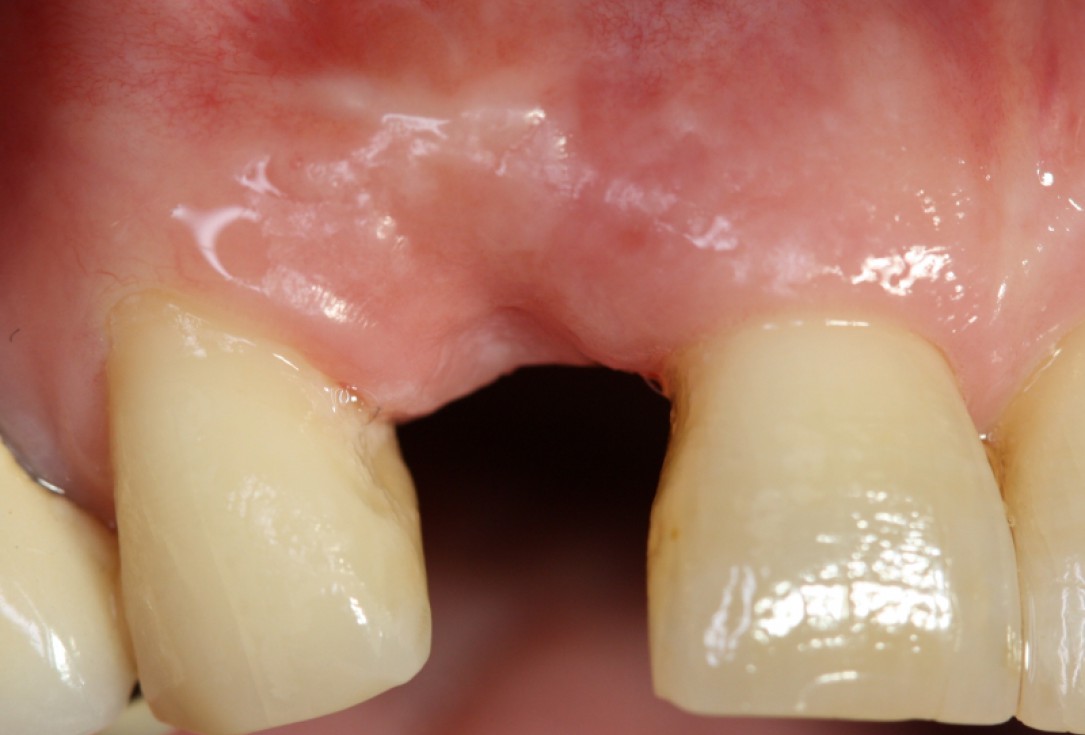

Initial situation: Inflammated tooth #12